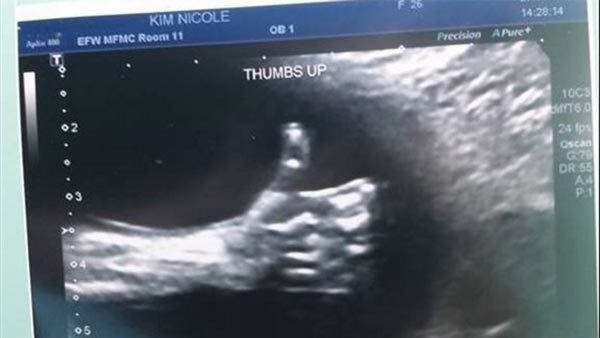

Bức ảnh siêu âm gây sửng sốt

Vợ chồng Nicole và Tony Kim phát hiện mình sắp có thêm em bé ngay sau khi anh chồng Tony bị mất việc trong ngành dầu khí. Tuy nhiên, gia đình đã nhận được một tín hiệu hy vọng bất ngờ từ đưa con chưa chào đời của họ.